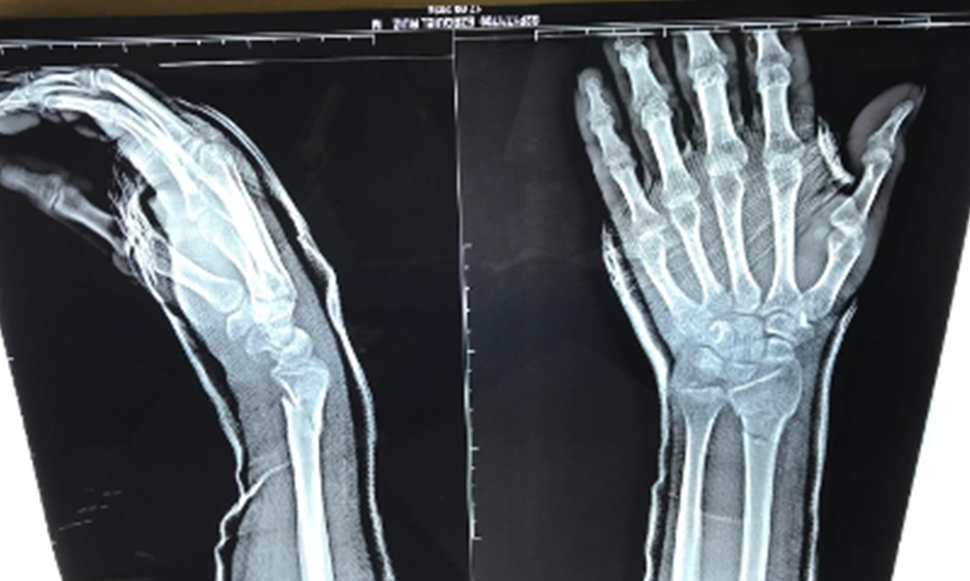

La Organización Mundial de la Salud (OMS), estima que 12% de las fracturas originadas principalmente en caídas y accidentes de tráfico, conllevan a discapacidades que pueden terminar con años potenciales de vida productivos. El crédito por la descripción del modelo de fractura más común que afecta el extremo distal del radio lo posee Sir Abraham Colles quien describió la fractura en el 1814, y desde entonces lleva su nombre (Enseñat, 2021). La fractura de Colles, también llamada de Colles-Pouteau, es una fractura que se produce en el radio a menos de 2,5 cm de la muñeca. Es una de las fracturas más frecuentes, especialmente en mujeres mayores de 60 años que además pueden padecer osteoporosis (Romero, 2009).